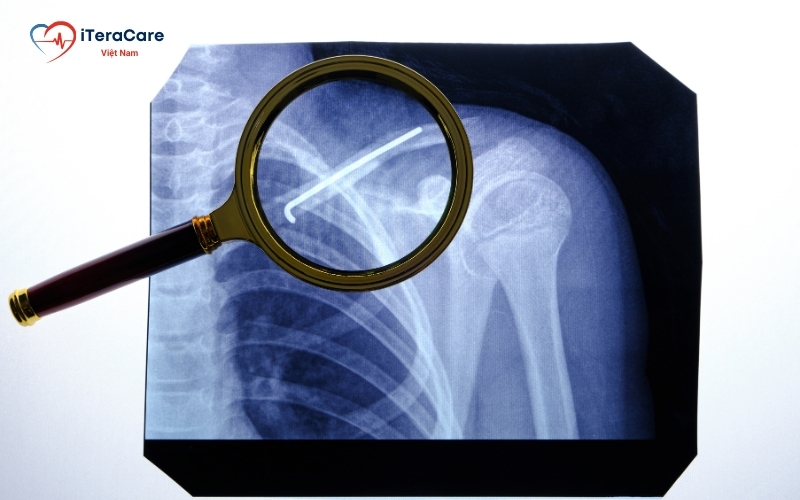

Phẫu thuật (Điều trị xâm lấn)

- Áp dụng cho trường hợp gãy xương có di lệch nhiều, gãy hở hoặc có nguy cơ tổn thương thần kinh, mạch máu.

- Bác sĩ sẽ sử dụng nẹp vít hoặc đinh nội tủy để cố định xương.

- Sau phẫu thuật, bệnh nhân cần thực hiện vật lý trị liệu để phục hồi chức năng vai.